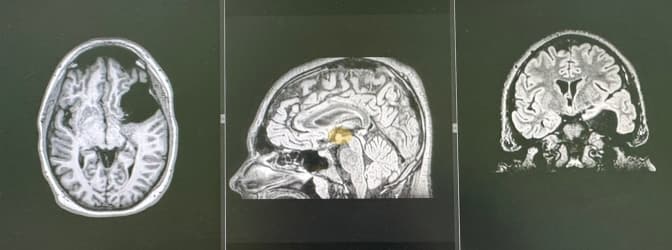

Львівські нейрохірурги прооперували підлітка з рідкісною пухлиною мозку

Львівські нейрохірурги видалили гігантську пухлину мозку чоловіку, який збирався їхати на фронт